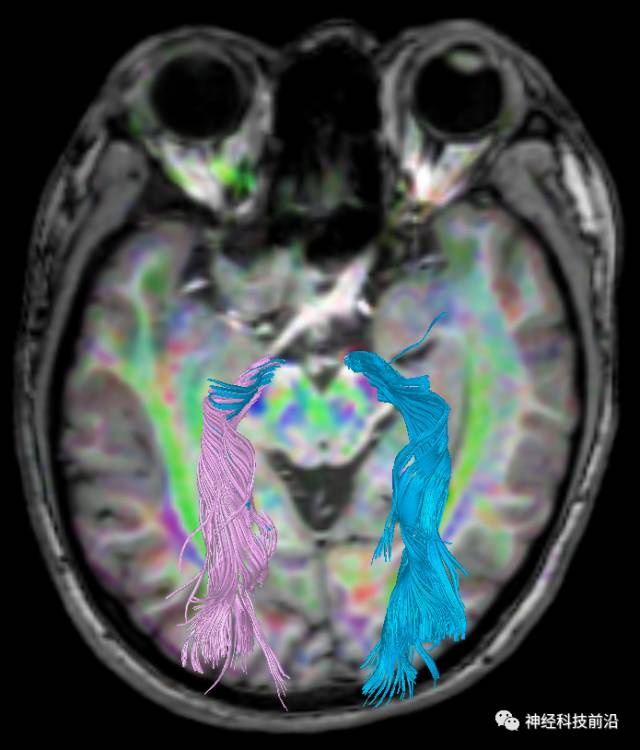

下面为皮质脑桥束的走形方位

皮质脑桥束与脑干高信号(黄色)纤维束

终上所述:脑干高信号为一近环形纤维束,内囊后肢高信号为皮质脑桥束,皮质脊髓束在中脑位置略靠后。高信号位于中脑前缘,是皮质脑桥束的位置所在,另外有部分桥连纤维。